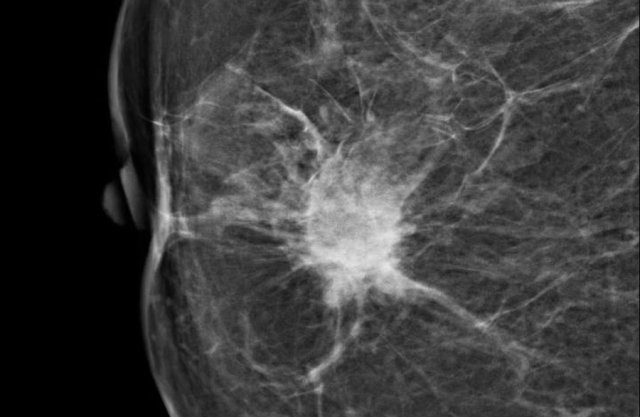

Here a hyperdense mass with an irregular shape and a spiculated margin.

Notice the focal skin retraction.

This was reported as BI-RADS 5 and proved to be an invasive ductal carcinoma.